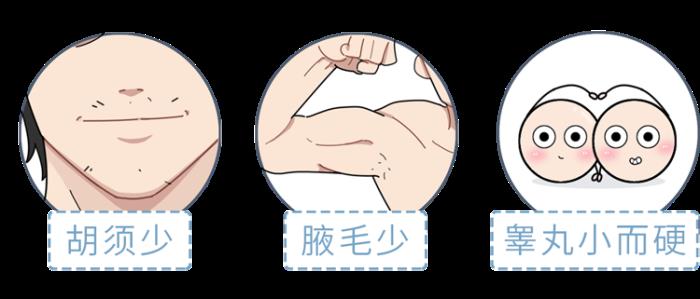

如果各位除了喉结不明显外

还伴随着这些症状

那就需要注意了

有可能是患了克氏综合征